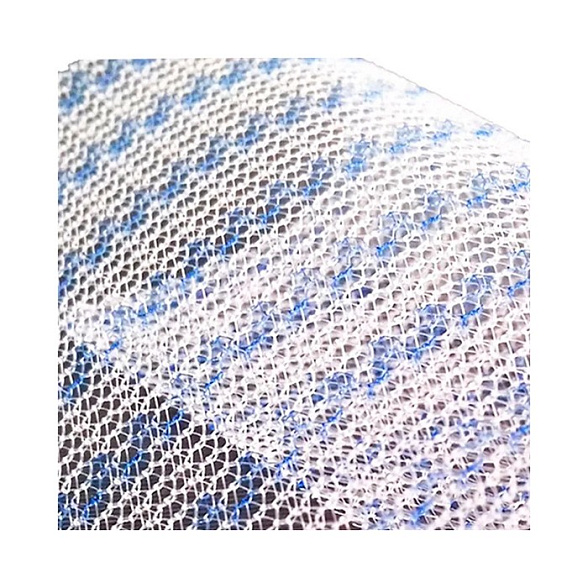

Полипропиленовая хирургическая сетка ЭСФИЛ тяжелый от компании «Линтекс» — это современный высокотехнологичный имплантат, предназначенный для надежного и долговечного укрепления тканей в ходе сложных реконструктивных операций. Изделие специально разработано для ситуаций, требующих повышенной механической прочности и стабильности.

Сетка ЭСФИЛ тяжелый обладает увеличенной плотностью и массой, что обеспечивает исключительную прочность на разрыв и минимальную послеоперационную деформацию. Это делает её оптимальным выбором для пластики обширных и сложных дефектов, где критически важна надежная и постоянная поддержка.

- Высокая механическая прочность: Увеличенная плотность полипропиленового монофиламента гарантирует устойчивость к нагрузкам и предотвращает растяжение имплантата со временем.

- Оптимальная интеграция с тканями: Структура сетки способствует активному прорастанию соединительной ткани (фиброзной инкорпорации), что создает единый прочный анатомический комплекс.

| Материал | Полипропилен (монолитная монофиламентная нить) |

| Тип плетения | Трикотажное |

После имплантации пористая структура сетки заполняется фибробластами и коллагеновыми волокнами организма пациента. Это приводит к прочному сращению (инкорпорации) имплантата с собственными тканями, создавая единый укрепляющий каркас.